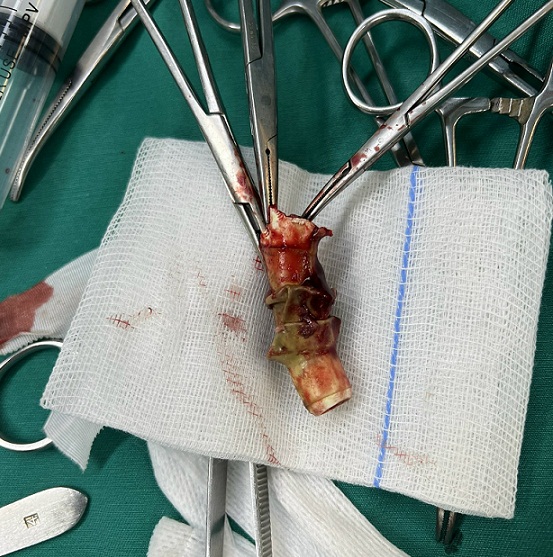

Đó là bệnh nhân Nguyễn Mạnh T (67 tuổi, ở Thanh Hóa). Bệnh nhân có tiền sử hẹp khí quản sau tai nạn giao thông, được mở khí quản vĩnh viễn 11 năm trước, bệnh nhân được hướng dẫn và tự thay nòng của canuyn mở khí quản hàng ngày. Từ khi mở khí quản, bệnh nhân không đi khám và chưa thay canuyn lần nào. Khoảng 14 giờ ngày 17/10/2022, bệnh nhân ho cơn, gãy canuyn mở khí quản và rơi vào trong đường thở, được cấp cứu tại Bệnh viện tỉnh Thanh Hóa. Bệnh nhân còn khó thở nhiều, ho đờm, không sốt, đau tức ngực, sau đó được chuyển Bệnh viện Hữu nghị Việt Đức, chẩn đoán Dị vật khí quản, phế quản gốc (P); tiên lượng khó khăn trong can thiệp lấy dị vật và được chuyển đến Trung tâm Hô hấp – Bệnh viện Bạch Mai trong tình trạng tỉnh, ho lọc xọc đờm, không sốt, khó thở nhẹ, huyết động ổn định. Chụp cắt lớp vi tính ngực có dựng hình khí phế quản cho thấy hình ảnh dị vật dạng ống trong khí quản và phế quản gốc (P), kích thước 5 x 1,5 cm, tắc hoàn toàn khí quản phía trên lỗ mở khí quản.

Hình ảnh chụp cắt lớp vi tính, dị vật đường thở